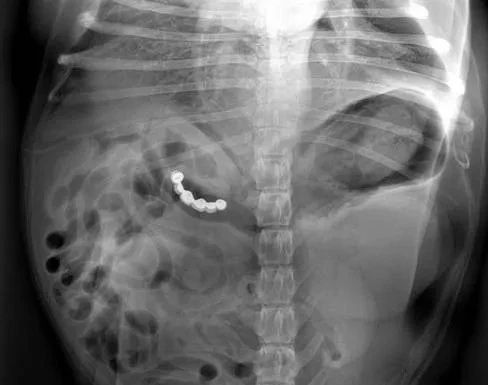

有这样一位心大的铲屎官,不小心居然把珍贵的结婚戒指弄丢了。满屋子找结婚戒指,一无所获。最后不得不动用金属探测仪来找那枚丢失的戒指。

房间里的每个角落都仔仔细细地探测了一遍,还是没有任何发现。有时候就是那么无奈,在铲屎官准备放弃的时候,家里的一只狗狗靠近探测仪,居然发出了警报。

戒指被狗狗吃了?铲屎官下意识闪过这样的念头。到医院检查后发现,戒指竟然真的在狗狗肚子里。

一番折腾,铲屎官总算拿回了戒指,狗狗也为这次吞食异物受了不少罪。